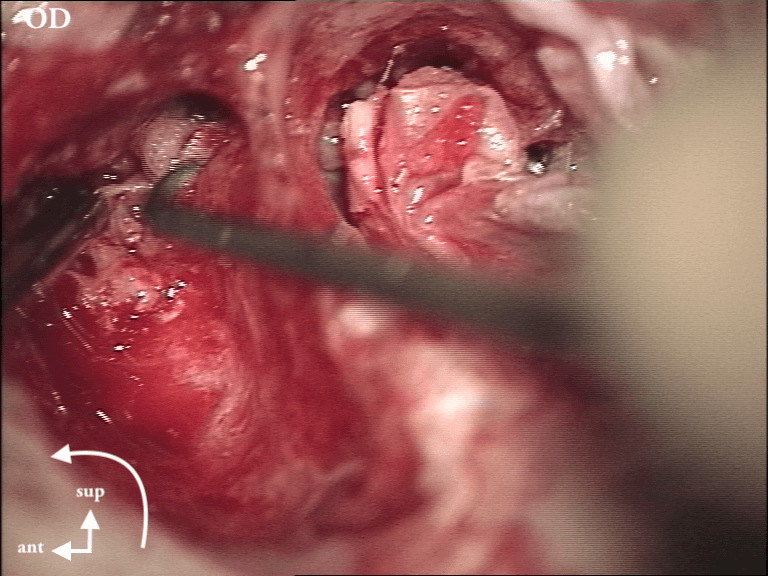

Epithélium stratifié, kératinisé et squameux présent dans l’oreille moyenne, "croissance progressive de peau dans l’oreille", "skin in the wrong place": la peau malade du tympan va détruire tout sur son passage: le tympan lui-même, les osselets, le cadre osseux jusqu'à la méninge. Là il faut bien utiliser toutes ses connaissances sémiologiques d'otoscopie pour faire le diagnostic, qui est plus facile que l'otite atéléctasique, en raison de la présence de squames.

Cela touche adultes & enfants.

Le/la patient·e avait attendu quelques mois avant de revenir: le cholestéatome a englobé tout le malléus:

Myringoplastie: